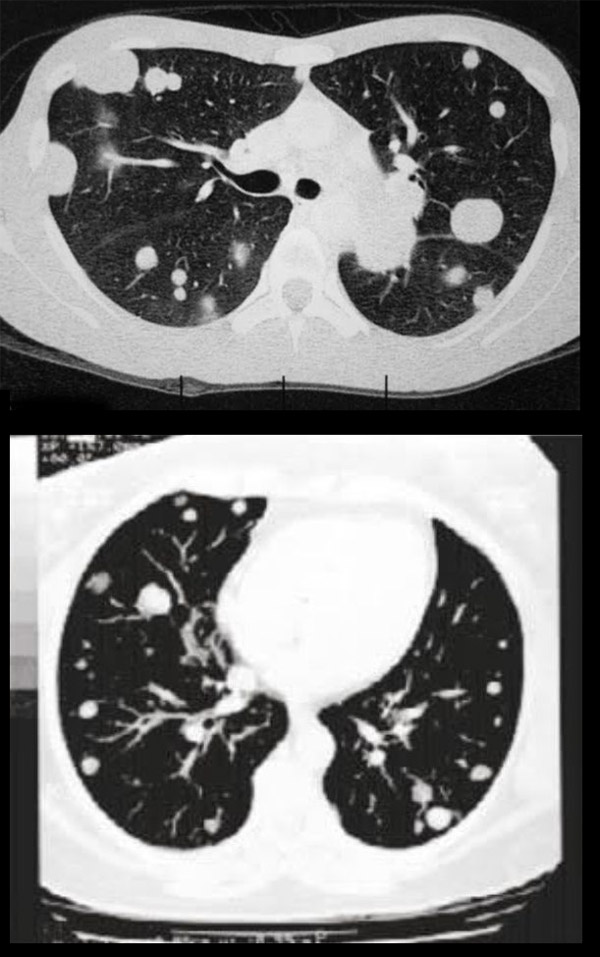

Nódulo Pulmonar Solitário

O Nódulo Pulmonar Solitário é uma lesão discreta. Ele tende a ser encontrado nos exames periódicos, como, por exemplo, em uma tomografia da região do tórax ou, até mesmo, em uma radiografia.